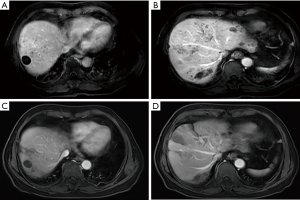

Treatment efficacy is shown in Table 2. After treatment with sorafenib and sequential regorafenib, 18 patients showed tumor progression, of which nine were treated with TACE combined with regorafenib and sintilimab, and the other nine continued to receive TACE combined with regorafenib. Five patients in the PD-1 group achieved a PR, three achieved SD, and one patient had PD after 1 month of treatment. The overall response rate (ORR) was 55.6% and the disease-control rate (DCR) was 88.9% (Table 2). One patient achieved a complete response (CR) after 6 months of therapy and another achieved a PR approaching a CR after 3 months of therapy in the PD-1 group (Figures 2,3). In the continued TACE–regorafenib group, four patients achieved PR, one achieved SD, and four patients achieved PD after 1 month of treatment. The ORR was 44.4% and the DCR was 55.6% (Table 2). No patients achieved CR after therapy, and there was a significant difference in the DCR between the two groups (P<0.05).

Our results show TACE combined with regorafenib and sintilimab confers a significant benefit when compared with continued TACE combined with regorafenib after the failure of second-line treatment with regorafenib. TACE combined with regorafenib and sintilimab had a higher DCR and was more effective than continued TACE plus regorafenib in patients with advanced HCC. Previous studies have confirmed regorafenib combined with PD-1 antibody is effective, with one showing a promising ORR of 28% in the first-line treatment of HCC (14). These results indicate TACE + regorafenib + sintilimab has an advantage over continued TACE combined with regorafenib alone. Regorafenib is a VEGFR inhibitor which inhibits JAK1/2-STAT1 and MAPK signaling, which could subsequently increase PD-L1 expression in tumors and increase intratumoral CD8+ T-cell infiltration by normalizing the tumor vasculature and improving the efficacy of the PD-1 antibody (11,15). This explains the significant difference in DCR between the two groups in our study (88.9% vs. 55.6%). However, we also found there was no significant difference in ORR between the two groups (55.6% vs. 44.4%), with four patients in the continued TACE combined with regorafenib group receiving the efficacy of PR. In other words, TACE combined with regorafenib was still effective after the failure of second-line treatment with regorafenib. This may be because the efficacy of TACE treatment differs according to patients’ physical strength and liver function. However, one patient achieved a CR and another achieved a PR approaching a CR in follow-up treatment in the TACE + regorafenib + sintilimab group, while the other group had no such efficacy. Therefore, TACE combined with regorafenib and sintilimab produced a benefit compared with continued TACE combined with regorafenib.